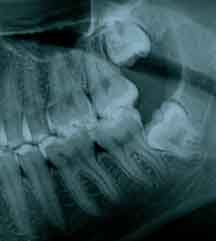

Para saber se a pessoa vai ter ou não os dentes do siso e se eles vão causar algum problema, é necessário um exame radiográfico.

A radiografia panorâmica ou tomografia são os mais utilizados. Além de mostrar a presença ou não dos mesmos, mostram sua relação com os órgãos vizinhos, tais como dentes, nervo alveolar inferior e cavidade sinusal.

A idade ideal para avaliarmos e acompanharmos a evolução, através de radiografia panorâmica é por volta dos 16 anos.

ASPECTO DE SISO INCLUSO: